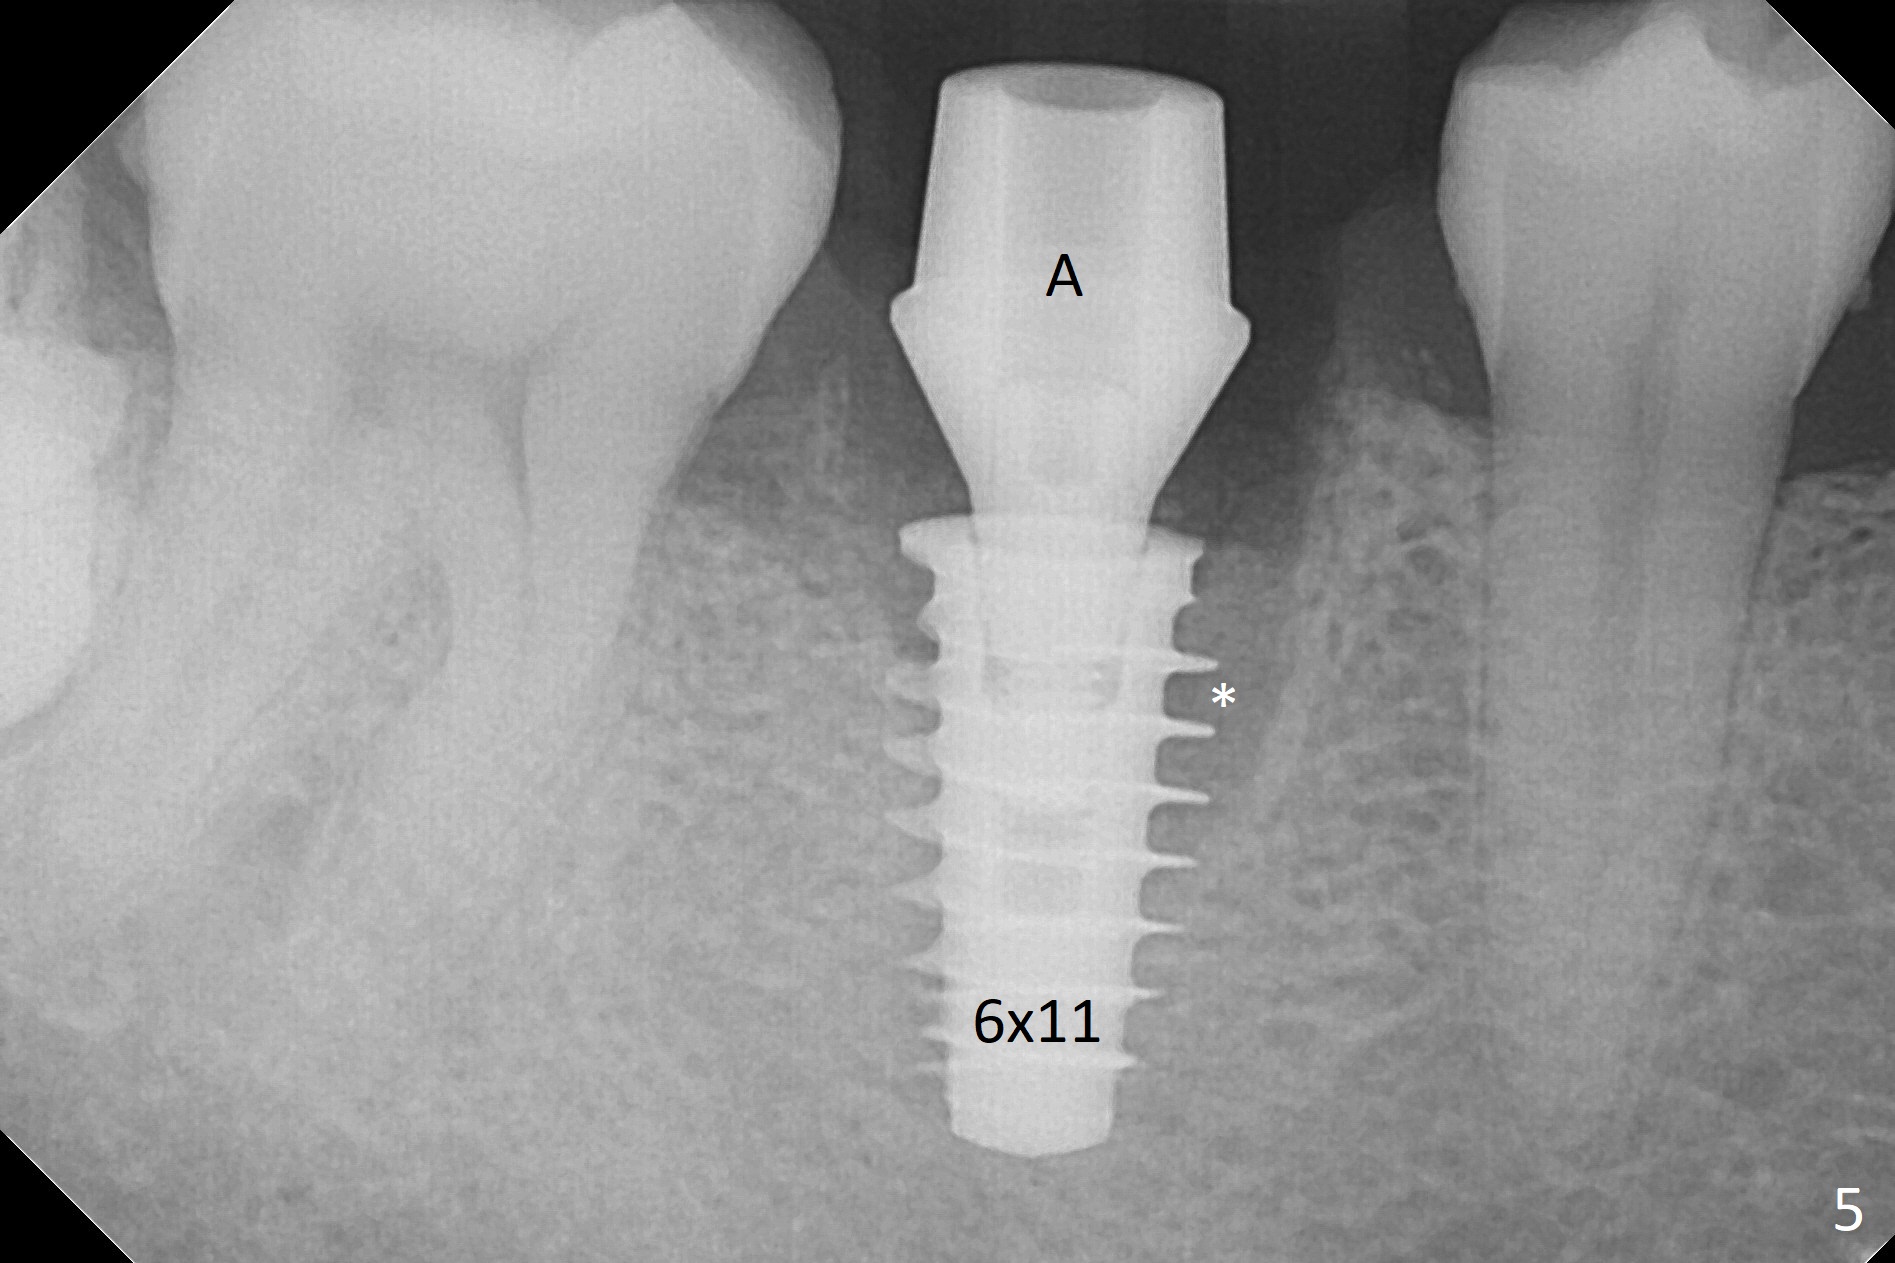

After removal of the residual roots at #30 (Fig.1), a thin septum (Fig.2 *) is removed with Rongeur (Fig.3). Following use of 4.8 mm Magic Drill, a 5x9 mm dummy implant is placed (Fig.4). To reduce socket gap (*), a 6 mm IBS implant is inserted with >50 Ncm (Fig.5). What is unexpected is heavy reduction in the height of a 6.5x4(3) mm abutment (A) because of the short crown height of the lower posterior teeth (Fig.1) and supraeruption of the tooth #3. The immediate provisional is unstable postop. The remade one dislodges soon, so does the abutment (Fig.6, 3 months postop). It appears that bone pattern in the distal socket changes.